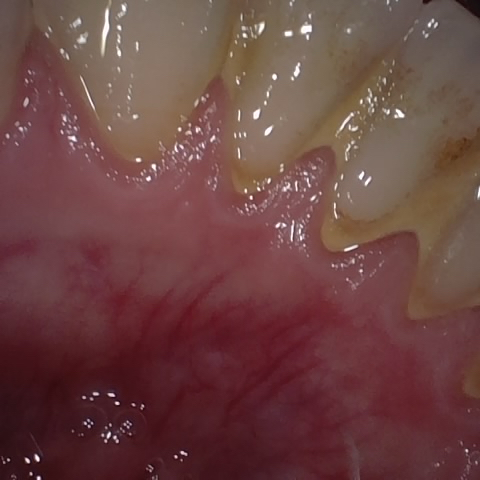

Annotated as "Good"